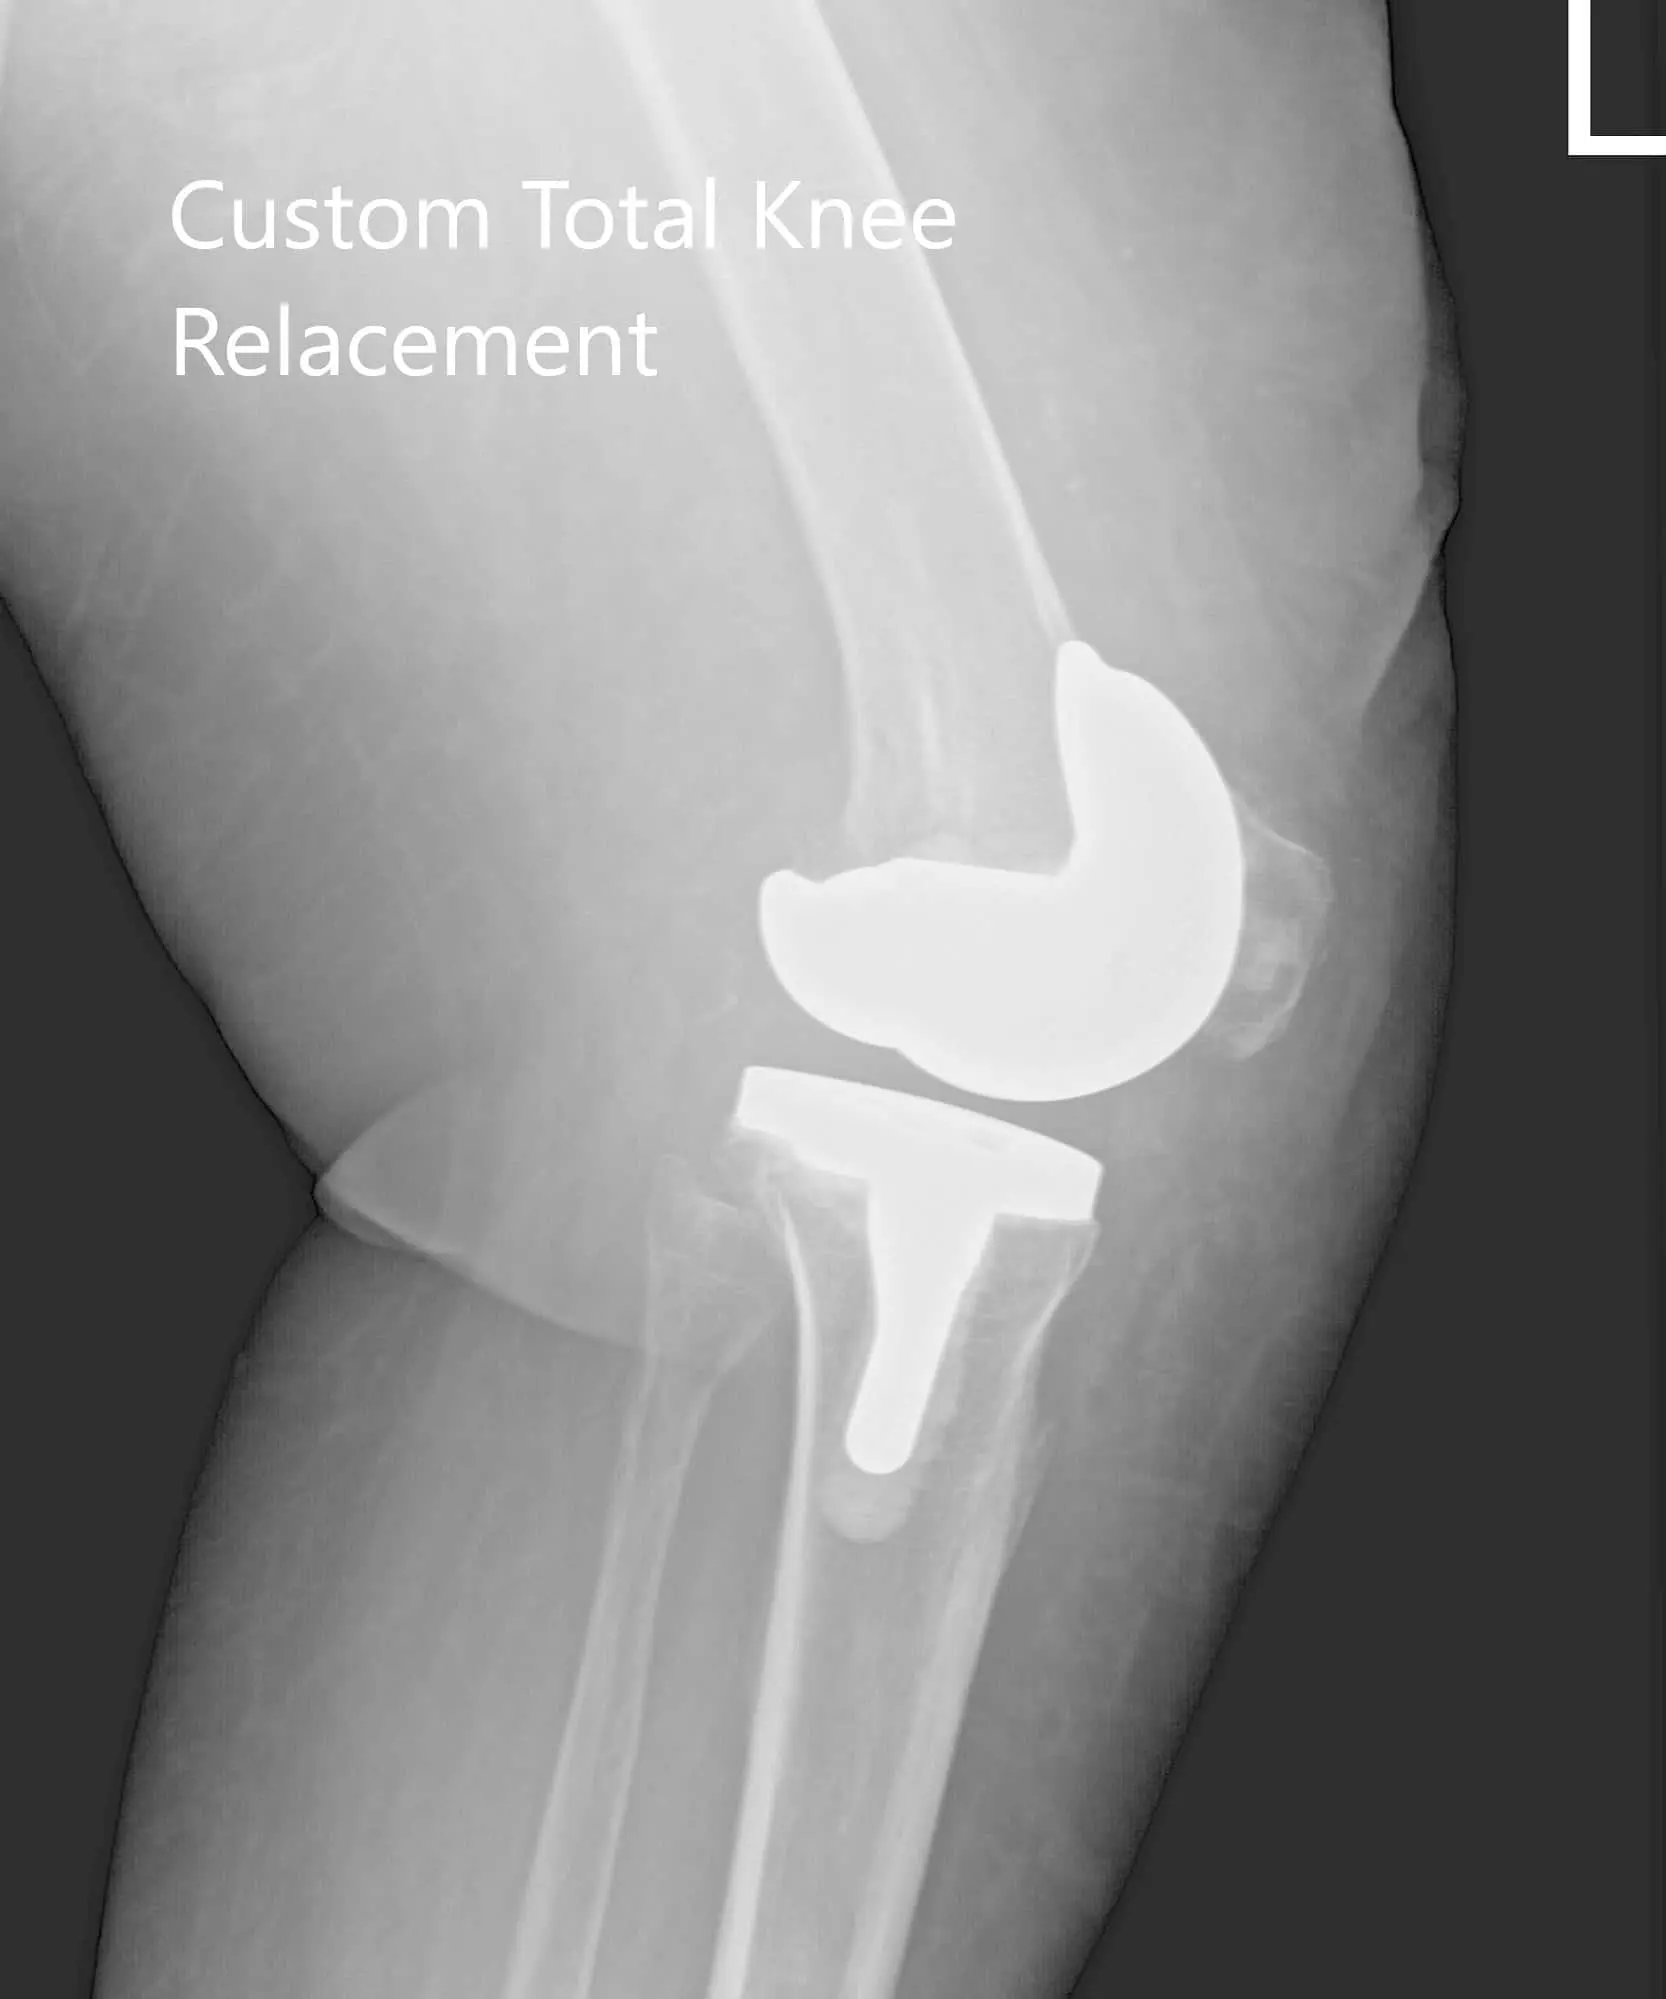

OPERATION: Left custom total knee replacement.

IMPLANTS USED: Custom femur and Custom tibia with a 29 mm patella with PS poly.

Postoperative X-ray showing AP and lateral images of the left knee